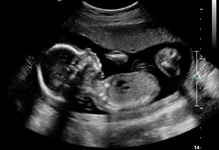

23 haftalık gebelik, hamileliğin ikinci trimesterinin sonlarına yaklaşıldığı bir dönemi ifade eder. Bu süre zarfında, hem anne hem de bebek için birçok önemli gelişim ve değişiklik yaşanmaktadır. Bu makalede, 23 haftalık gebelik dönemindeki fiziksel ve duygusal değişimlerin yanı sıra, bebeğin gelişimi, anne adayının sağlığı ve dikkat edilmesi gereken hususlar ele alınacaktır. Bebeğin Gelişimi23 haftalık gebelikte bebek, hızla büyümeye devam etmekte ve birçok önemli gelişim sürecinden geçmektedir. Bu dönemde, bebeğin gelişimiyle ilgili bazı önemli noktalar şunlardır: